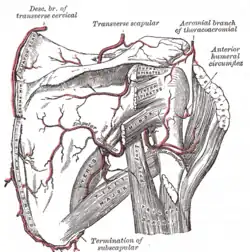

Artérias escapular e circunflexa.

Artérias escapular e circunflexa. -